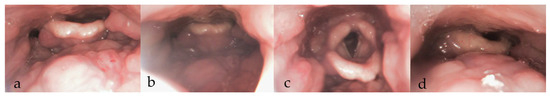

3.3. During DISE (Figure 1)

3.3.8. Documentation